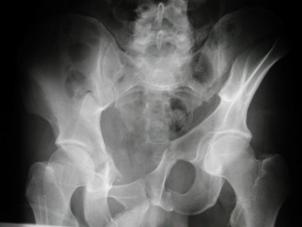

TRAUMATISMELE PELVIENE

Traumatism

pelvian Hemipelviectomie dreapta posttraumatica

Banda de stabilizare Dallas Fractura de bazin. Radiografie in

incidenta AP

Fractura de bazin

. Radiografie in incidenta AP Fractura de spina